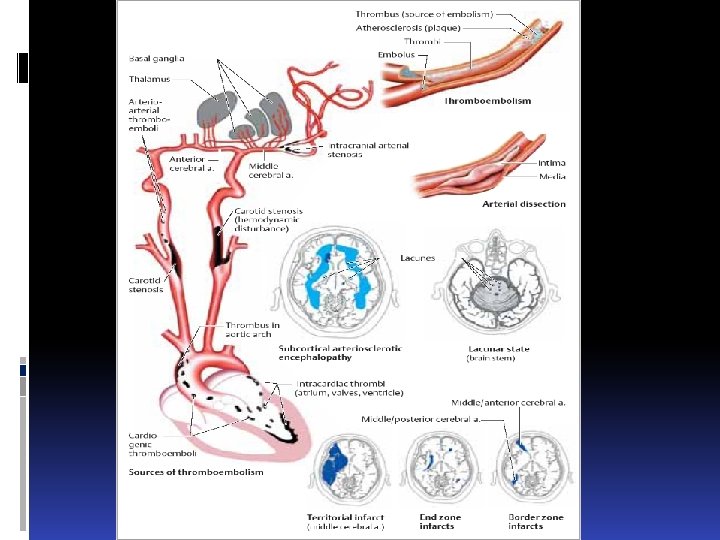

ИШЕМИЧЕСКИЕ ИНСУЛЬТЫ ischemic strokes Атеротромботический Эмболический (кардиоэмболический, тромбоэмболический, жировая эмболия, газовая эмболия, эмболия околоплодными водами) Гемодинамический Лакунарный Гемореологическая микроокклюзия Aterotrombotic Embolic Hemodynamic Lacunar Hemoreological microocclusion

ИШЕМИЧЕСКИЕ ИНСУЛЬТЫ ischemic strokes Атеротромботический Эмболический (кардиоэмболический, тромбоэмболический, жировая эмболия, газовая эмболия, эмболия околоплодными водами) Гемодинамический Лакунарный Гемореологическая микроокклюзия Aterotrombotic Embolic Hemodynamic Lacunar Hemoreological microocclusion

The Contents to lectures: Stroke A stroke is an acute focal or global impairment of brain function resulting from a pathological process (e. g. thrombus, embolus, vessel rupture) of the blood vessels. Its causes, in order of decreasing frequency, are ischemia (80%), spontaneous intracerebral or intraventricular hemorrhage (15%), and subarachnoid hemorrhage (5 %). The signs and symptoms of stroke are usually not specific enough to enable identification of its etiology without further diagnostic studies. CT, MRI, cerebrovascular ultrasonography, ECG, and laboratory testing are usually needed.

The Contents to lectures: Stroke A stroke is an acute focal or global impairment of brain function resulting from a pathological process (e. g. thrombus, embolus, vessel rupture) of the blood vessels. Its causes, in order of decreasing frequency, are ischemia (80%), spontaneous intracerebral or intraventricular hemorrhage (15%), and subarachnoid hemorrhage (5 %). The signs and symptoms of stroke are usually not specific enough to enable identification of its etiology without further diagnostic studies. CT, MRI, cerebrovascular ultrasonography, ECG, and laboratory testing are usually needed.

Types of infarct. There are three basic types of brain infarct, distinguished from each other by the caliber of the occluded arteries: Territorial infarcts are mainly produced by occlusions of the main trunks or major branches of cerebral arteries (cerebral macroangiopathy), which may be due to thrombosis, embolism, or other causes. The infarct includes both cortex and subcortical white matter and sometimes the basal ganglia and thalamus (Fig. 6. 12). It is usually possible to infer which vessel has been occluded from the pattern of neurological deficits that are produced.

Types of infarct. There are three basic types of brain infarct, distinguished from each other by the caliber of the occluded arteries: Territorial infarcts are mainly produced by occlusions of the main trunks or major branches of cerebral arteries (cerebral macroangiopathy), which may be due to thrombosis, embolism, or other causes. The infarct includes both cortex and subcortical white matter and sometimes the basal ganglia and thalamus (Fig. 6. 12). It is usually possible to infer which vessel has been occluded from the pattern of neurological deficits that are produced.